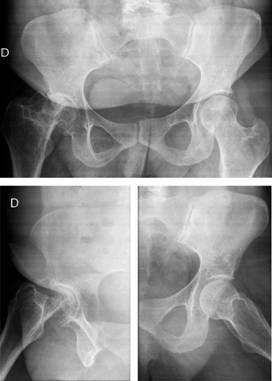

En la exploración física general destaca una estatura baja y las escleróticas azules. No presenta hipoacusia ni alteraciones dentales. Se observa una dismetría de extremidades de tres centímetros y una actitud en rotación interna de la extremidad inferior derecha. La puntuación en la escala Merle D’Aubigné-Postel para la cadera derecha es de 3.3.4., con una importante limitación para la movilidad y las actividades de la vida diaria. En las radiografías se observa la presencia de coxartrosis derecha secundaria a la fractura de fémur proximal en la infancia (Figura 1).

Figura 1: Radiografías AP de pelvis A. y axial de caderas B. coxartrosis derecha secundaria a fractura de fémur proximal intracapsular a los nueve años.